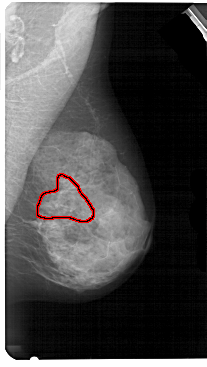

A_1605_1.LEFT_MLO

FILE: A_1605_1.LEFT_MLO.OVERLAY

TOTAL_ABNORMALITIES 1

ABNORMALITY 1

LESION_TYPE CALCIFICATION TYPE PLEOMORPHIC DISTRIBUTION SEGMENTAL

ASSESSMENT 4

SUBTLETY 3

PATHOLOGY BENIGN

TOTAL_OUTLINES 1

BOUNDARY